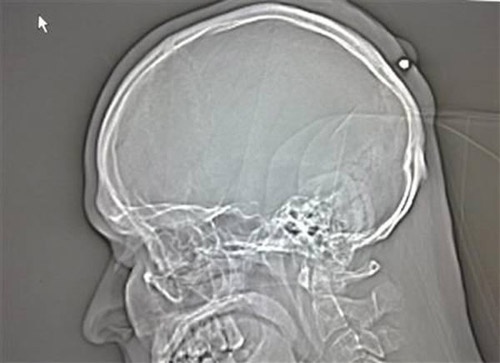

Ông Balan khi sang Đức sinh sống, làm ăn đã không hay biết mình từng bị đạn bắn vào đầu trong lúc say bí tỉ tại một buổi tiệc cách đó 5 năm. Bác sĩ đã phát hiện ra viên đạn cỡ nòng 0,22 mm, nằm phía sau đỉnh đầu khi chàng trai này đến bệnh viện khám vì cho rằng mình bị khối u cần loại bỏ.

Nhắc lại những gì đã xảy ra trước đó, người đàn ông 35 tuổi chỉ nhớ rằng vào khoảng năm 2004 hoặc 2005, ông từng có cảm giác như bị một thứ gì đó đánh mạnh vào đầu trong một buổi tiệc đêm mừng năm mới. Tuy nhiên, do đã say khướt nên ông hoàn toàn quên sạch chuyện này và để viên đạn tồn tại sau đỉnh đầu suốt 5 năm sau đó mà không hay biết.